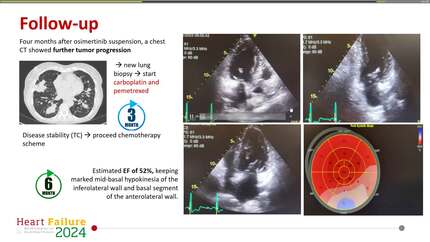

Osimertinib-induced heart failure.